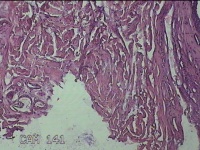

右侧颜面部结节

性别

男

年龄

49岁

临床诊断

皮脂腺囊肿

一般病史

发现右侧颜面部结节5年余。

标本名称

大体所见

灰白暗红色组织1x0.7x0.3cm一块,表面带梭形皮肤1x0.5cm,皮下见结节0.9x0.7x0.3cm一个,切开结节呈实性,切面灰白暗红色,质中。

图4